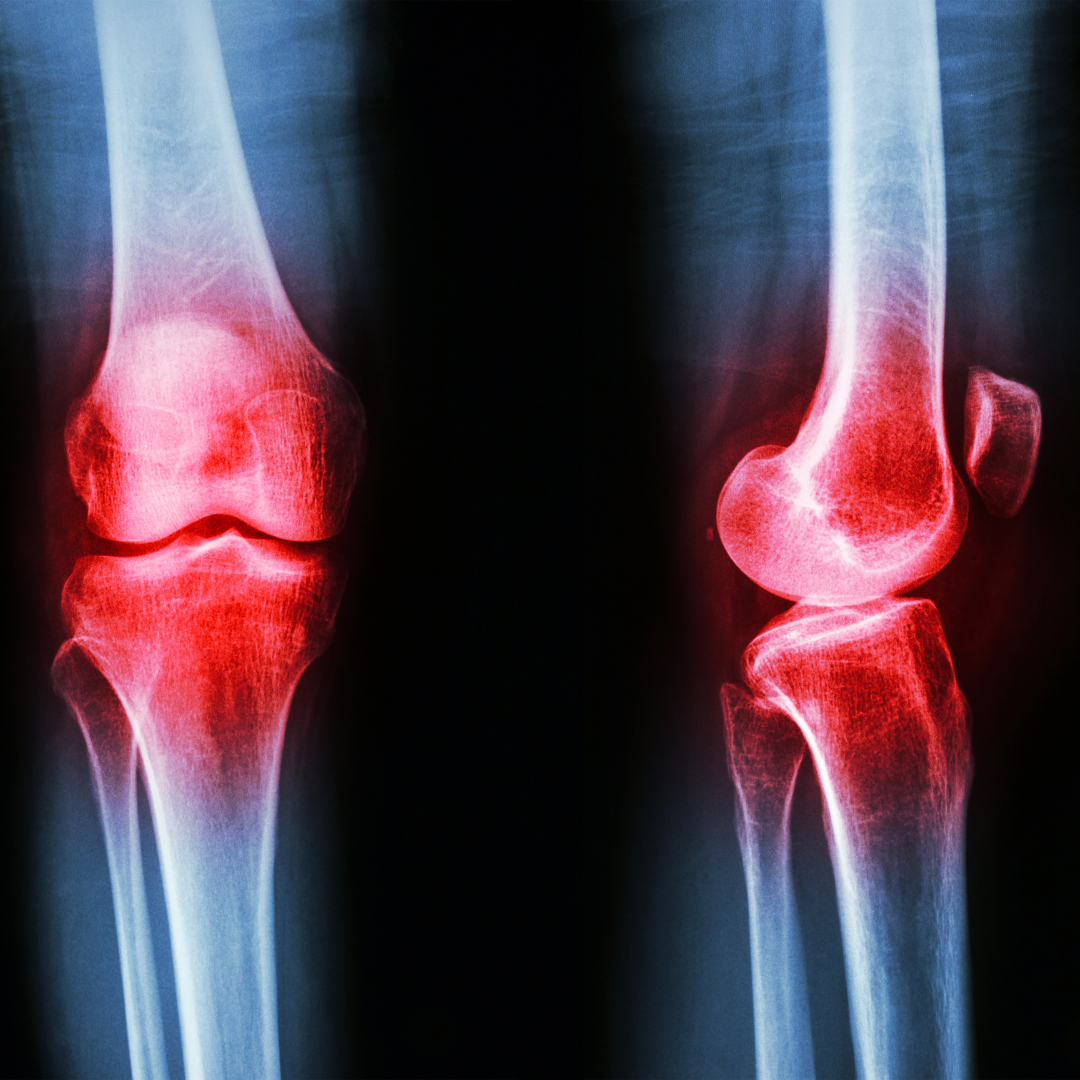

Articolazioni più colpite

Le sedi più frequenti sono:

-

Ginocchio (gonartrosi)